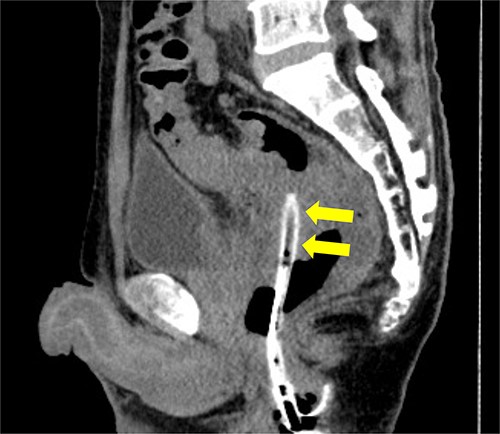

A 53-year-old Japanese man was admitted to the hospital with a chief complaint of buttock pain that lasted for 5 months and a recent weight loss of 8 kg, from 68 kg to 60 kg. He had no remarkable medical history. Digital rectal examination could not be performed because of severe pain. Laboratory findings revealed severe inflammation, indicated by an increased white blood cell count (16 790 cells/μL) and C-reactive protein (12.15 mg/dL). He was also undernourished with an albumin level of 2.7 g/dL. Tumor marker levels of carcinoembryonic antigen and cancer antigen 19–9 were within the normal ranges. Pelvic computed tomography (CT) showed contrast-enhanced thickening of the upper rectal wall and perirectal abscess (Fig. 1). Swollen lymph nodes were observed near the mesentery, but distant metastases were not detected. Rectal cancer accompanied by a pelvic abscess was then suspected. For the patient’s relief, sigmoid colonoscopy was performed under lumbar spinal anesthesia, which revealed a semicircular type 2 tumor in the upper rectum (Fig. 2a), and exclusion from outside the rectal wall on the anal side of the tumor at 7 cm from the anal verge (Fig. 2b). The colonoscope could not pass through the oral side of the tumor.

Contrast medium-enhanced CT upon admission in axial (a) and sagittal (b) sections. Irregular thickening of the rectal wall (arrowheads) and an accompanying pelvic abscess (arrows) are observed. No evident distant metastases are observed.